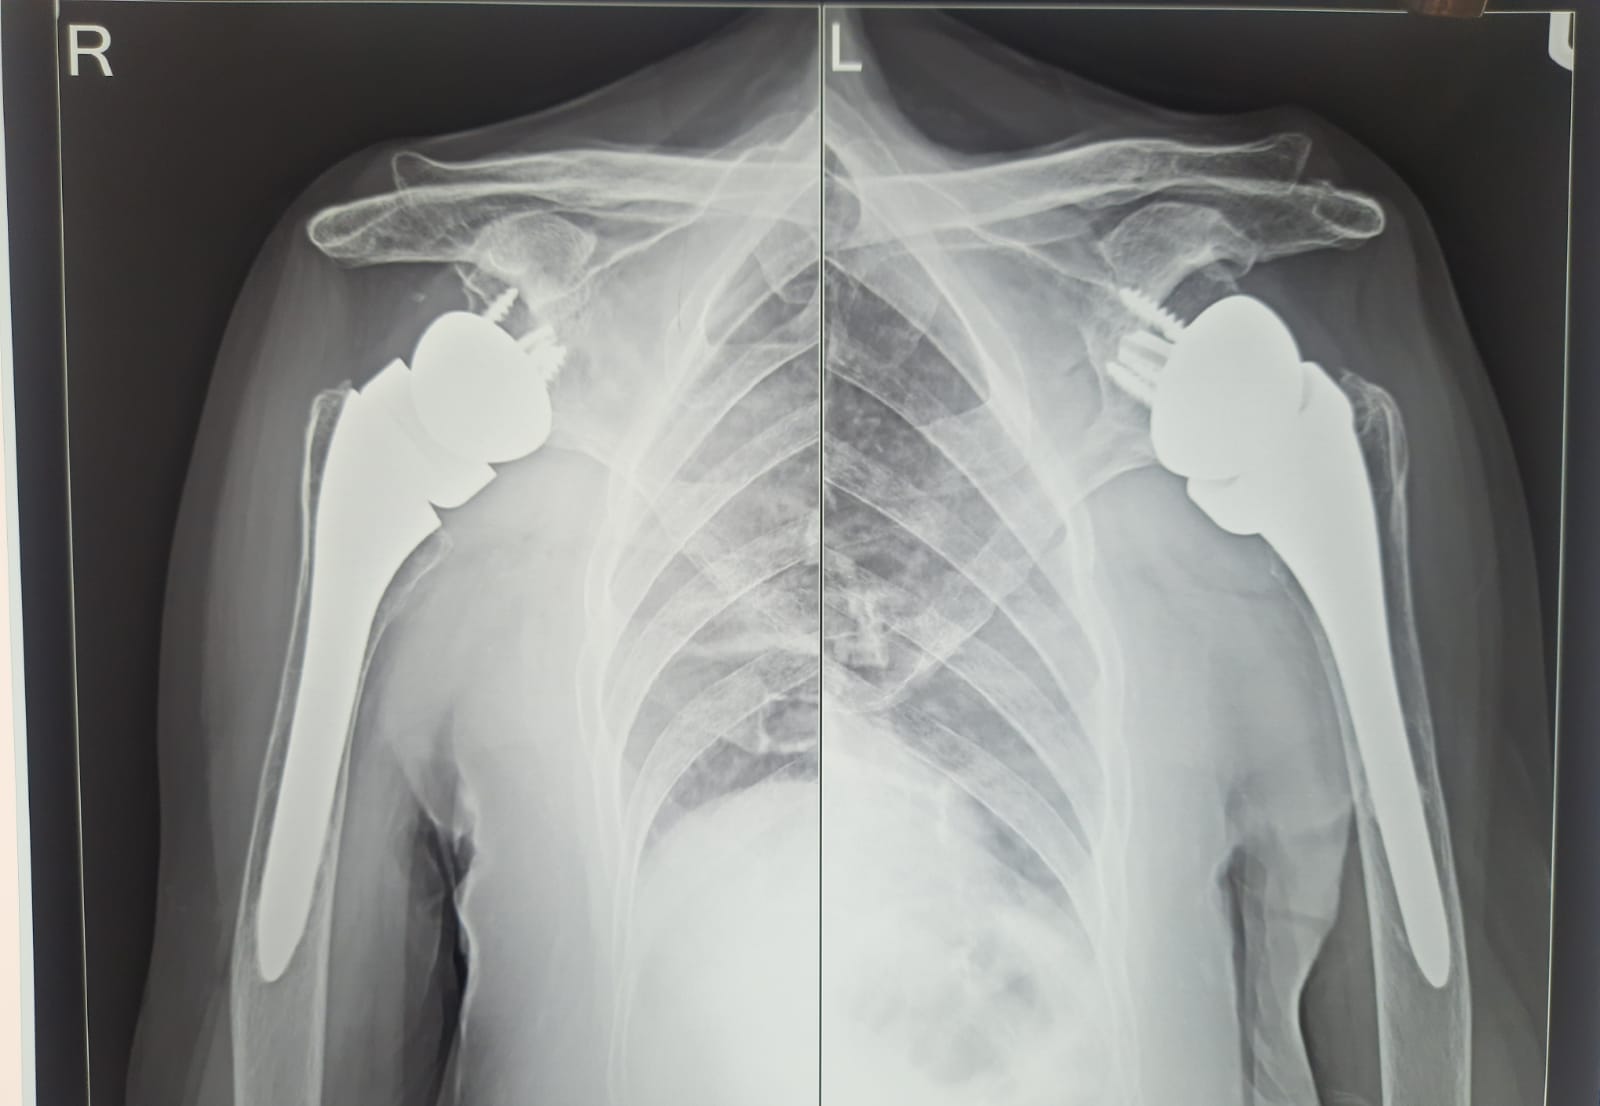

Bilateral Reverse Shoulder Replacement in an elderly lady, Who is now 85 years old. Right Reverse Shoulder done 8 years ago and left 4 years ago.

8 Years follow up Right RTSR, 4 Years follow up LEFT